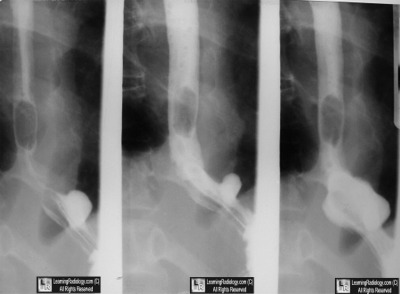

Images from Barium Esophagram

Inflammatory Polyp

- Uncommon polypoid lesions of the esophagus

- Most common mucosal lesion: squamous papilloma

- Most common submucosal lesion: leiomyoma

- Nearly all occur in the distal esophagus or esophagogastric junction

- Frequently associated with erosive esophagitis or ulcer

- No malignant potential reported